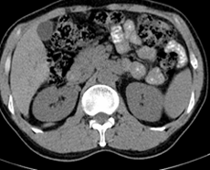

患者,男,57,常年不吃午饭,近一个月来腹部隐痛,无明显黄疸,明天进行增强扫描,图象另上传,麻烦各位帮忙一起看看讨论讨论

肝外胆管扩张,胰头增大,肠系膜上静脉似有包埋征象。

考虑:胰头占位性病变,建议增强进一步检查。

肝内外胆管扩张,胆管未端阻塞,建议mri检查

肝外胆管稍扩张,胰腺钩突略增大,但外形尚可,境界清楚。(常年不吃午饭)提示胰腺炎可能大,肿瘤第二步考虑。

胰头增大,胆总管增宽,考虑胰头癌可能性大,明天看增强片有助诊断.